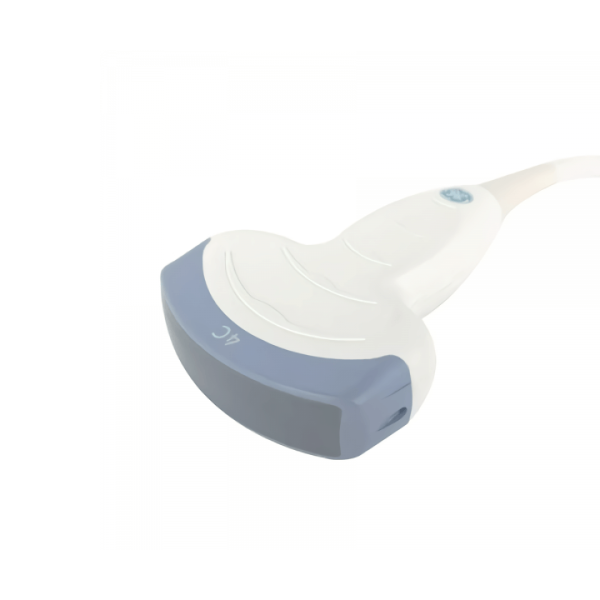

Совместимые датчики